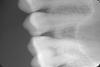

Tooth Опубликовано 29 сентября, 2009 Автор Поделиться Опубликовано 29 сентября, 2009 (изменено) Давайте снимок-там все будет видно(только на визиографе его сделайте пожалуйста-на маленькой пленке мало что видно) Фея, прилагаю прицельный снимок 25-го зуба с визиографа. Он посередине Повторюсь, моим врачом диагностирована начальная стадия кариеса в районе контакта с 24-ым. Врач сказал - сверлить рано, потому что область поражения как минимум в два раза меньше необходимой области препарирования зуба для качественной постановки пломбы и лучше пока понаблюдаться. Мне в декабре на очередной осмотр. Каково ваше мнение ? P.S. Я очень склонен верить своему доктору Изменено 29 сентября, 2009 пользователем Tooth Ссылка на комментарий

CToMaToJIor Опубликовано 29 сентября, 2009 Поделиться Опубликовано 29 сентября, 2009 Фея, прилагаю прицельный снимок 25-го зуба с визиографа. Он посередине Повторюсь, моим врачом диагностирована начальная стадия кариеса в районе контакта с 24-ым. Врач сказал - сверлить рано, потому что область поражения как минимум в два раза меньше необходимой области препарирования зуба для качественной постановки пломбы и лучше пока понаблюдаться. Мне в декабре на очередной осмотр. Каково ваше мнение ? P.S. Я очень склонен верить своему доктору На снимке кариеса нет ))) Ссылка на комментарий

zybnaya feya Опубликовано 29 сентября, 2009 Поделиться Опубликовано 29 сентября, 2009 Т.е. мой врач не зря НЕ направил меня делать снимок на визиографе т.к. начальный кариес в стадии пятна не идентифицируется по снимку, а только лишь визуально и поэтому стоит понаблюдаться несколько месяцев ? Спасибо, CToMaToJIor.Ну на 24 кариеса не видно на снимке. Но он есть на контакте между 25 и 26 Ссылка на комментарий

Tooth Опубликовано 30 сентября, 2009 Автор Поделиться Опубликовано 30 сентября, 2009 (изменено) Ну на 24 кариеса не видно на снимке. Но он есть на контакте между 25 и 26 Фея, что-то вы меня совсем запутали. Может конечно и я что-то не так расслышал и доктор имел в виду между 25 и 26. Точно уже не помню конечно Что наверняка помню, так это что речь шла о лечении 25 через несколько месяцев.А где вы увидели между 25 и 26 на снимке ? Вы имеете в виду чуть тёмное пятнышко в контактной зоне на эмали на 26 ? В этом случае скоро 25 и 26 лечить ? Или только какой-то из них (25) ? И в какой стадии кариес на данный момент по вашему мнению - действительно рано пока сверлить или пора ? Изменено 30 сентября, 2009 пользователем Tooth Ссылка на комментарий

zybnaya feya Опубликовано 30 сентября, 2009 Поделиться Опубликовано 30 сентября, 2009 Фея, прилагаю прицельный снимок 25-го зуба с визиографа. Он посередине Повторюсь, моим врачом диагностирована начальная стадия кариеса в районе контакта с 24-ым. Это вот про какой зуб вы спрашиваете????? Я вам и отвечаю на ваш вопрос 25 у вас на снимке посередине. Ссылка на комментарий